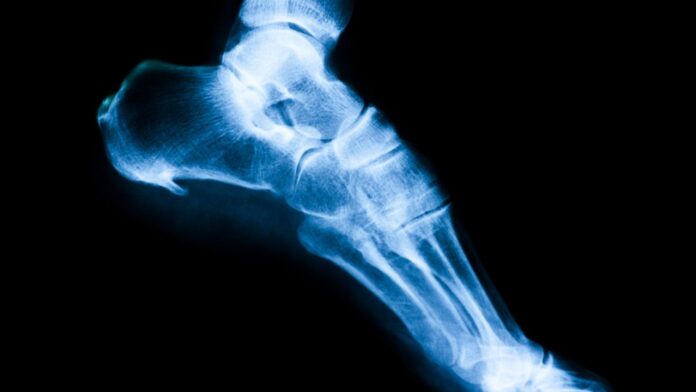

• activitatea fizică intensă se asociază și cu creșterea densității osoase, deci poate preveni osteoporoza.

• sedentarismul duce la pierderea rapidă a masei musculare; crește astfel riscul reducerii densității osoase, riscul de fracturi sau riscul de pierdere a echilibrului și cădere.